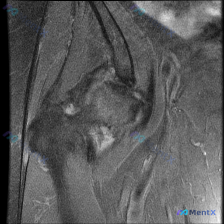

最近看到一个肩关节MRI轴位T2序列的病例,患者临床怀疑有盂唇病变,但影像分析结果显示: - 前、后盂唇形态完整,呈典型三角形低信号 - 未见明显断裂、撕脱或异常高信号 - 肩胛下肌肌腱、肱二头肌长头腱形态及信号也正常 这种影像与临床不符的情况该怎么考虑?大家第一反应会往哪个方向走?